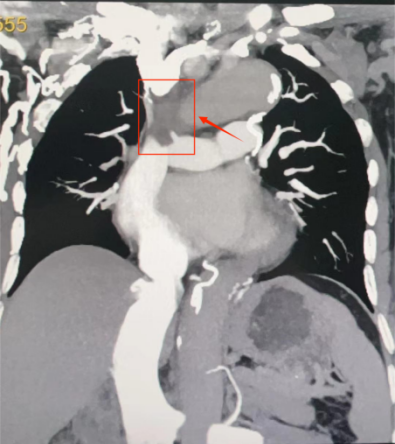

图片

术前CT可见上腔静脉受压